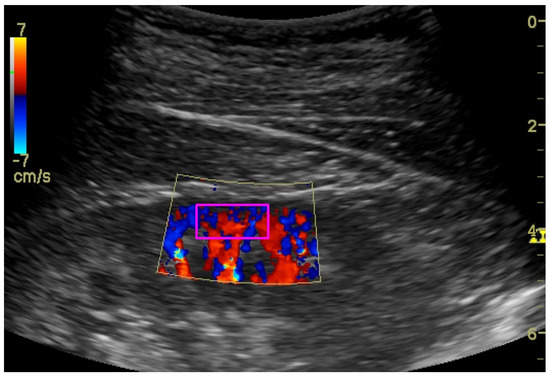

2.3. Kidney Ultrasound

| dRCP (cm/s) | 0.483 | 0.452 | 0.303 | 0.529 |